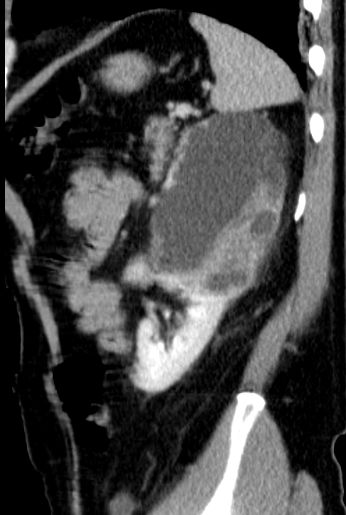

Urothelkarzinom der Niere 81-jährige Frau mit einem großen, die linke Niere einnehmendem Tumor. Histologie: Urothelkarzinom.

Die linke Nierenarterie ist von LK-Metastasen eingeschlossen.

Auch im Mediastinum große LK-Metastasen.